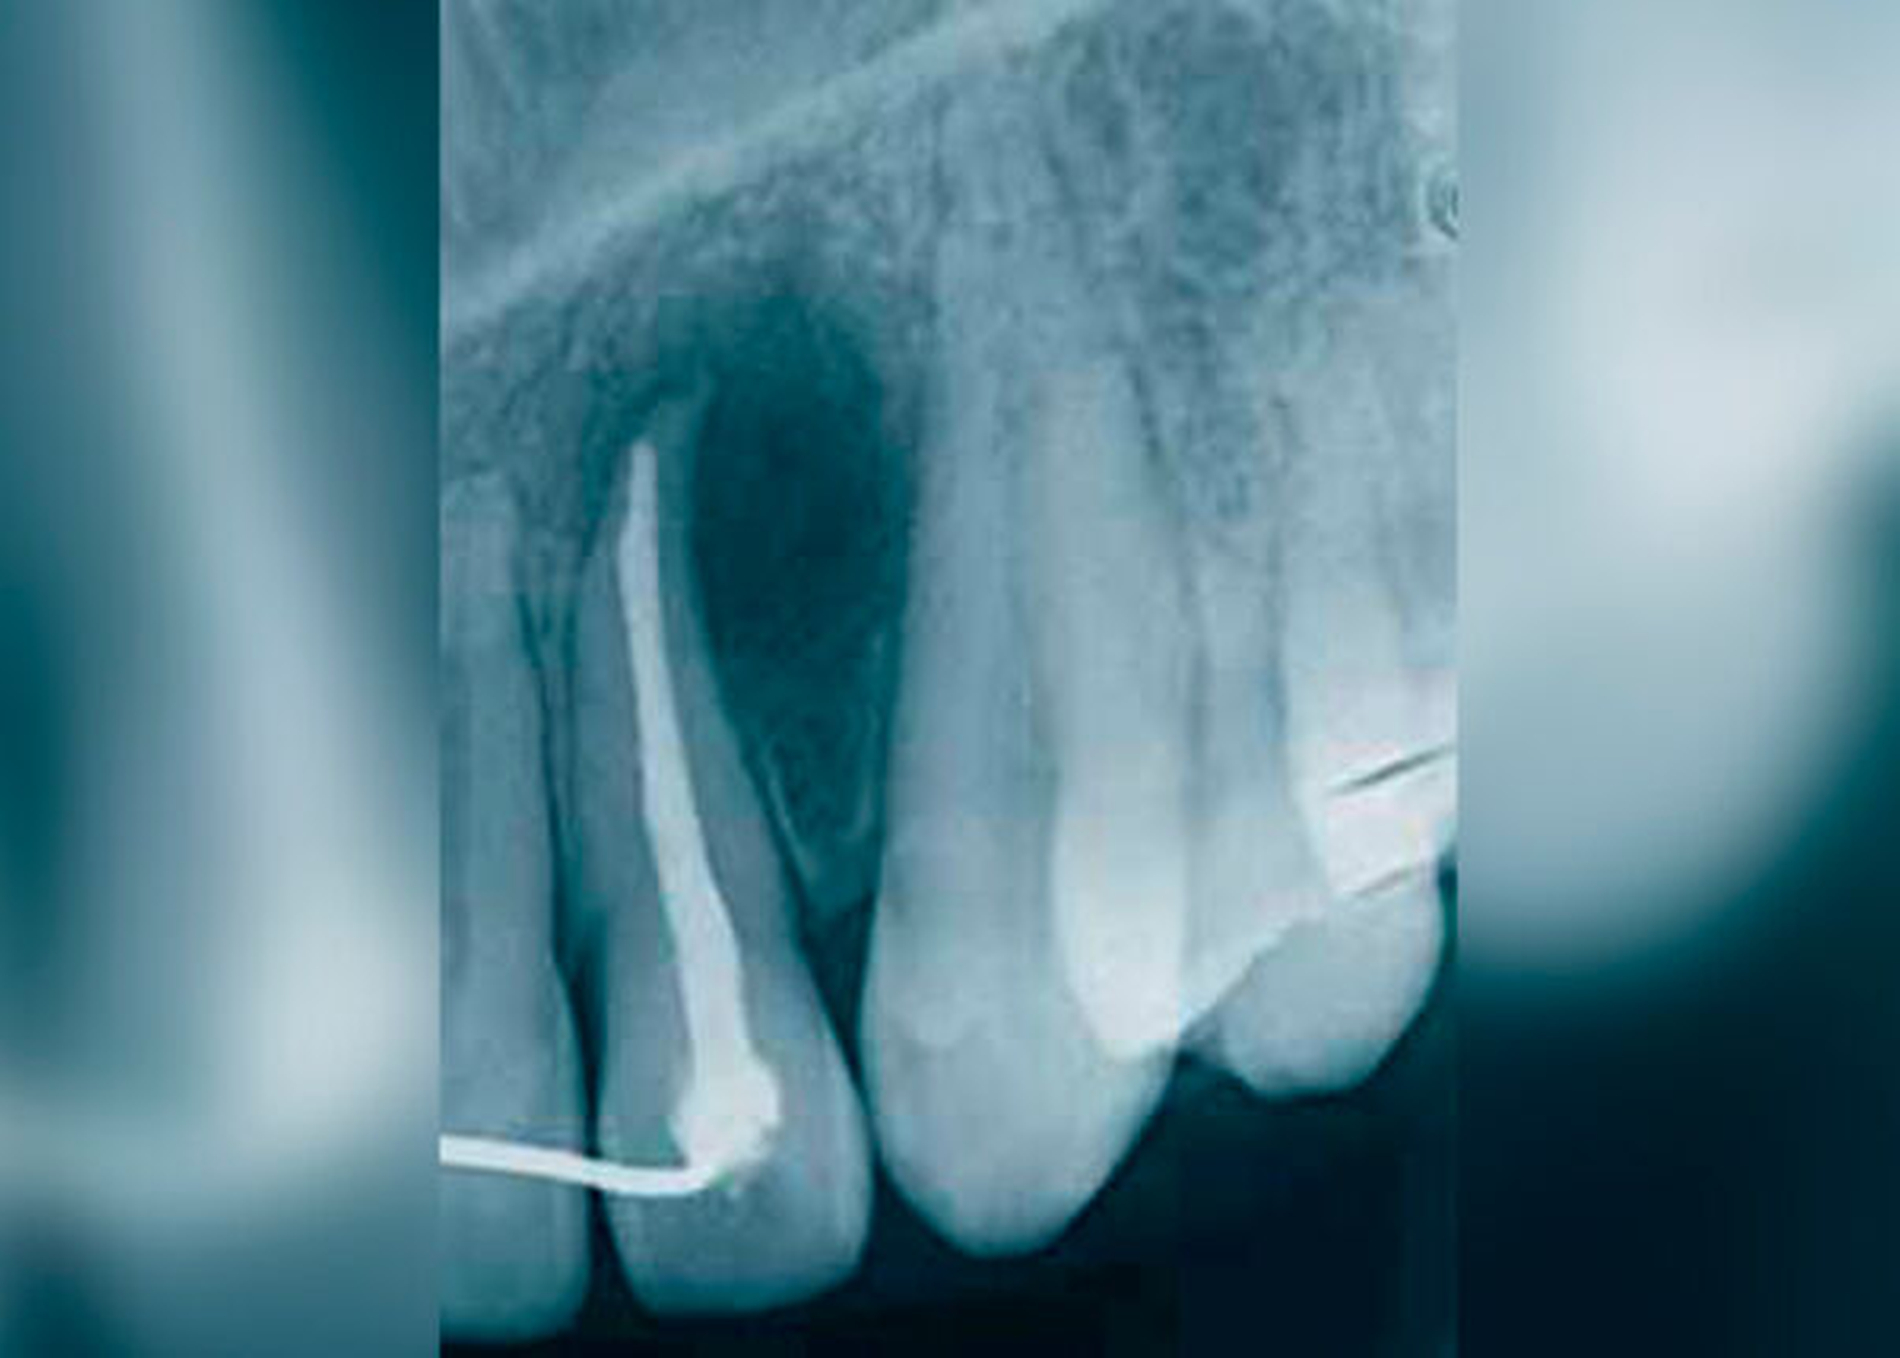

Die klinische und pathohistologische Evidenz spricht überzeugend dafür, dass Zysten im „Globulomaxillären Bereich“ radikuläre Zysten, laterale Parodontalzysten, odontogene Keratozysten [Christ, 1970], kalzifizierende odontogene Zysten, adenomatoide odontogene Tumore [Rosenberg & Cruz, 1963; Giansanti et al., 1970; Khan et al., 1977], odontogene Myxome [Rud, 1964; Taicher & Azaz, 1977], Ameloblastome [Aisenberg & Inman, 1960], zentrale Riesenzellgranulome oder hämorrhagische Knochenzysten [Peters & Wassow, 1968] sind (Abb. 6 bis 13).

Auch die Möglichkeiten von invaginierten Zähne [Galindo-Moreno et al., 2003] oder von apikalen Infektionen, die beim Foramen caecum oberer lateraler Inzisivi ihren Ursprung genommen haben, sollten in die Differentialdiagnose miteinbezogen werden. Zahninvaginationen kommunizieren häufig mit der Pulpa, was früher oder später zur Pulpanekrose und zur Parodontitis apicalis führen und eine GZ vortäuschen kann [Galindo-Moreno et al., 2003]. Eine Entstehungstheorie aus einer verkümmerten Zahnanlage im „Globulomaxillären Bereich“ klingt zwar verlockend, wurde aber in der Literatur bis heute nicht ausreichend untersucht.